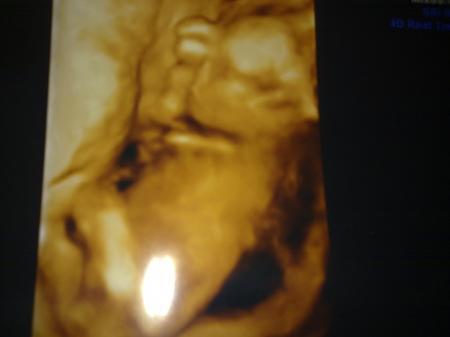

so,wie irina schon so lieb berichtete wird es wahrscheinlich ein kleines super süßes gesundes geliebtes bezauberndes glückliches baby mädchen. nach meinem traum,obwohl ich immer eher einen amerikanischen vornamen wie emily oder sonstwas haben wollte,soll unser schatz emma joy heißen. einen rosa strampler haben wir gekauft-aus optimistischen gründen....hoffe mein fa irrt sich nicht...ach und wenn-egal. die kleine war extrem wild und schlug um sich,trat aus und pinkelte los.lach ach ganz die mama....die kleine pipi emma. organe sind super..herz prima und durchblutung 1a.freu anbei 3 fotos.

und drei 3 mit hand am kopf-ach ich bin verliebt